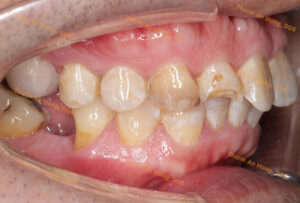

HÌNH ẢNH THỰC TẾ

Chỉnh khay dựng trục răng cối lớn hàm dưới